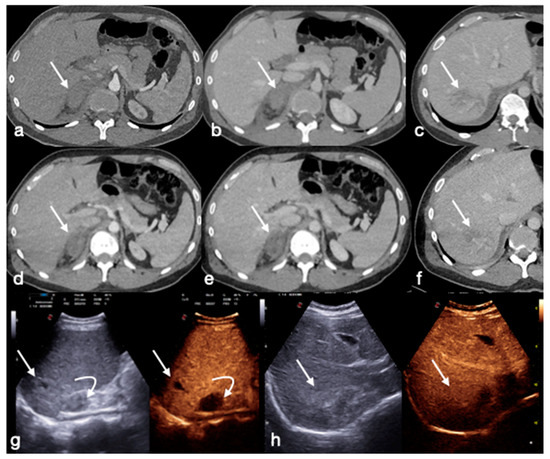

- Di Serafino, M.; Iacobellis, F.; Schillirò, M.L.; Ronza, R.; Verde, F.; Grimaldi, D.; Dell’Aversano Orabona, G.; Caruso, M.; Sabatino, V.; Rinaldo, C.; et al. The Technique and Advantages of Contrast-Enhanced Ultrasound in the Diagnosis and Follow-Up of Traumatic Abdomen Solid Organ Injuries. Diagnostics 2022, 12, 435. [Google Scholar] [CrossRef] [PubMed]

- Miele, V.; Piccolo, C.L.; Sessa, B.; Trinci, M.; Galluzzo, M. Comparison between MRI and CEUS in the follow-up of patients with blunt abdominal trauma managed conservatively. Radiol. Med. 2015, 121, 27–37. [Google Scholar] [CrossRef] [PubMed]